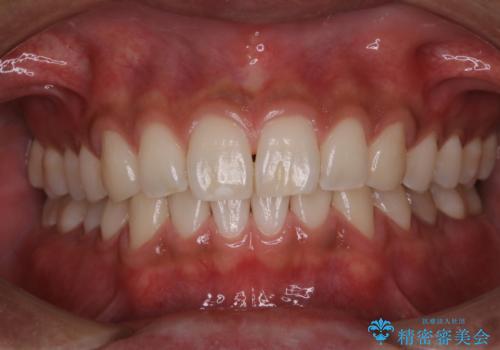

PMTCを行うことで、ご自身本来の歯の色になり自然な明るさになります。

口元が自然な明るさになることで、より清潔感のある印象になるため結婚式・行事やイベント前などにもPMTCを行うはおすすめです。

また、ホワイトニングを考えている場合も、まずはPMTCで汚れの除去を行って判断することをおすすめします。